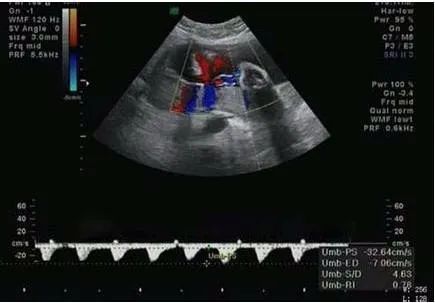

妊娠期为了保证母胎健康和宝宝正常的发育,所需要做的检查是很多的,一般当怀孕20周以后就可以做脐血流的检查,这也是检查项目之一。脐血流是指脐带中血液流动的情况,脐带中一般包括三条血管,其中两条是动脉,一条是静脉。脐血流是反映了这三条血管的情况,血流一般通过S/D来进行表达,S一般是指收缩期血流速度,D一般是指舒张期的血流速度。这个数值反映了脐带血流的阻力。数值越高反应血流阻力越大速度越慢。

S/D正常情况下和孕周相关,不能大于相应孕周的参考范围的最大值,如果大于相应孕周参考范围最大值,往往提示血流慢了胎儿可能存在缺氧或者血液供应不足的情况,这种情况有可能引起胎儿生长发育不全。因此在孕期做b超的时候一定要注意脐血流是不是正常,如果异常,应及时检查原因。

一般在20周以前检测脐血流意义不大,随着孕周的增加,脐血流呈下降趋势,脐血流正常值在24周时其平均值为3.5,上限为4.25,超过上限为异常。孕28周后S/D应小于3,从孕25周到41周,大多数 孕妈 的S/D比值几乎呈直线从2.8降至2.2左右。一般妊娠晚期S/D值小于或等于3.0...为正常。